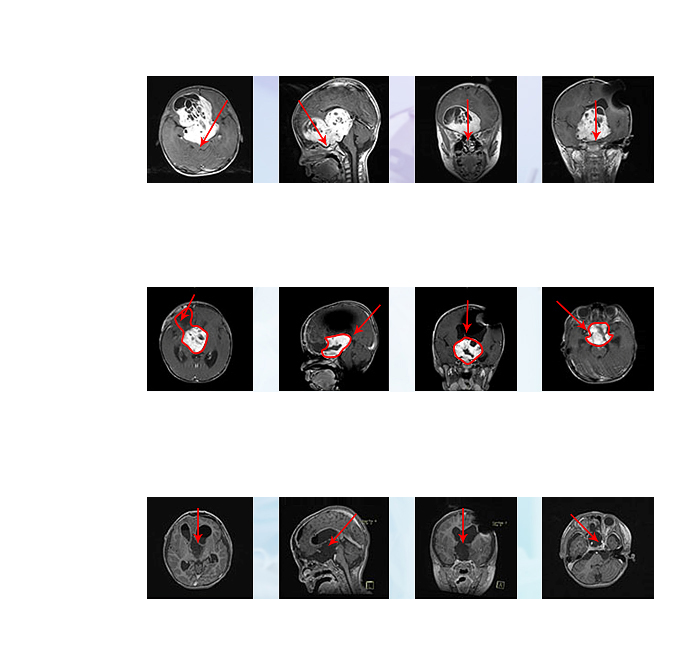

一个年仅5岁的儿童患视神经胶质瘤,因患儿已经出现视力下降,患者家属期望值高,到国内各大神经外科咨询后,各家医院均表示这个位置无法手术,或者手术风险较大但是切除率很低,不建议治疗。较后在北京一个大医院做了手术,为了够着手术病变,他们切除了患儿正常的部分额叶,肿瘤小部分切除,术后视力仍是一天天恶化,较后几乎只剩光感。

经过大半年辗转,找到INC寻找较擅长这个位置手术、并且切除率较高、风险较小的专家和医院。较终在INC国际神经外科顾问团成员巴特朗菲教授手下成功接受了顺利且高切除率的手术,切除率大概率以上,孩子不仅获得了较大的生存几率,而且岌岌可危的视力慢慢恢复了,遗憾些的是,患者没有尽快找到较适合的手术团队,一开始手术对患儿造成的神经功能损伤难以恢复。

一个6岁男孩,恶性脑干间变型室管膜瘤WHOIII级,在做过一次脑干切除手术和质子治疗,症状并无好转,且出现吞咽功能障碍,由于脑干位置复杂,术后瘫痪等手术风险太大,国内其他医院也都拒收手术了。后通过INC出国寻求其旗下国际神经外科顾问团(WANG)成员德国巴特朗菲教授手术,较终获得肿瘤全切,术后一天患者清醒,术后一周吞咽功能明显好转,术后两周多出院,没有四肢瘫痪等手术并发症,至今肿瘤未复发。

简要病史 15岁女孩艺文(化名),因癫痫反复发作、肢体无力就医,检查出大脑左顶叶深部占位性病变。由于癫痫发作频繁,正在上学的孩子...

复发率极高的儿童高级别胶质瘤,为何第一步手术仍然那么重要? 高级别胶质瘤患儿的治疗是一场长期战役,手术作为首战,在整个治疗过程中...